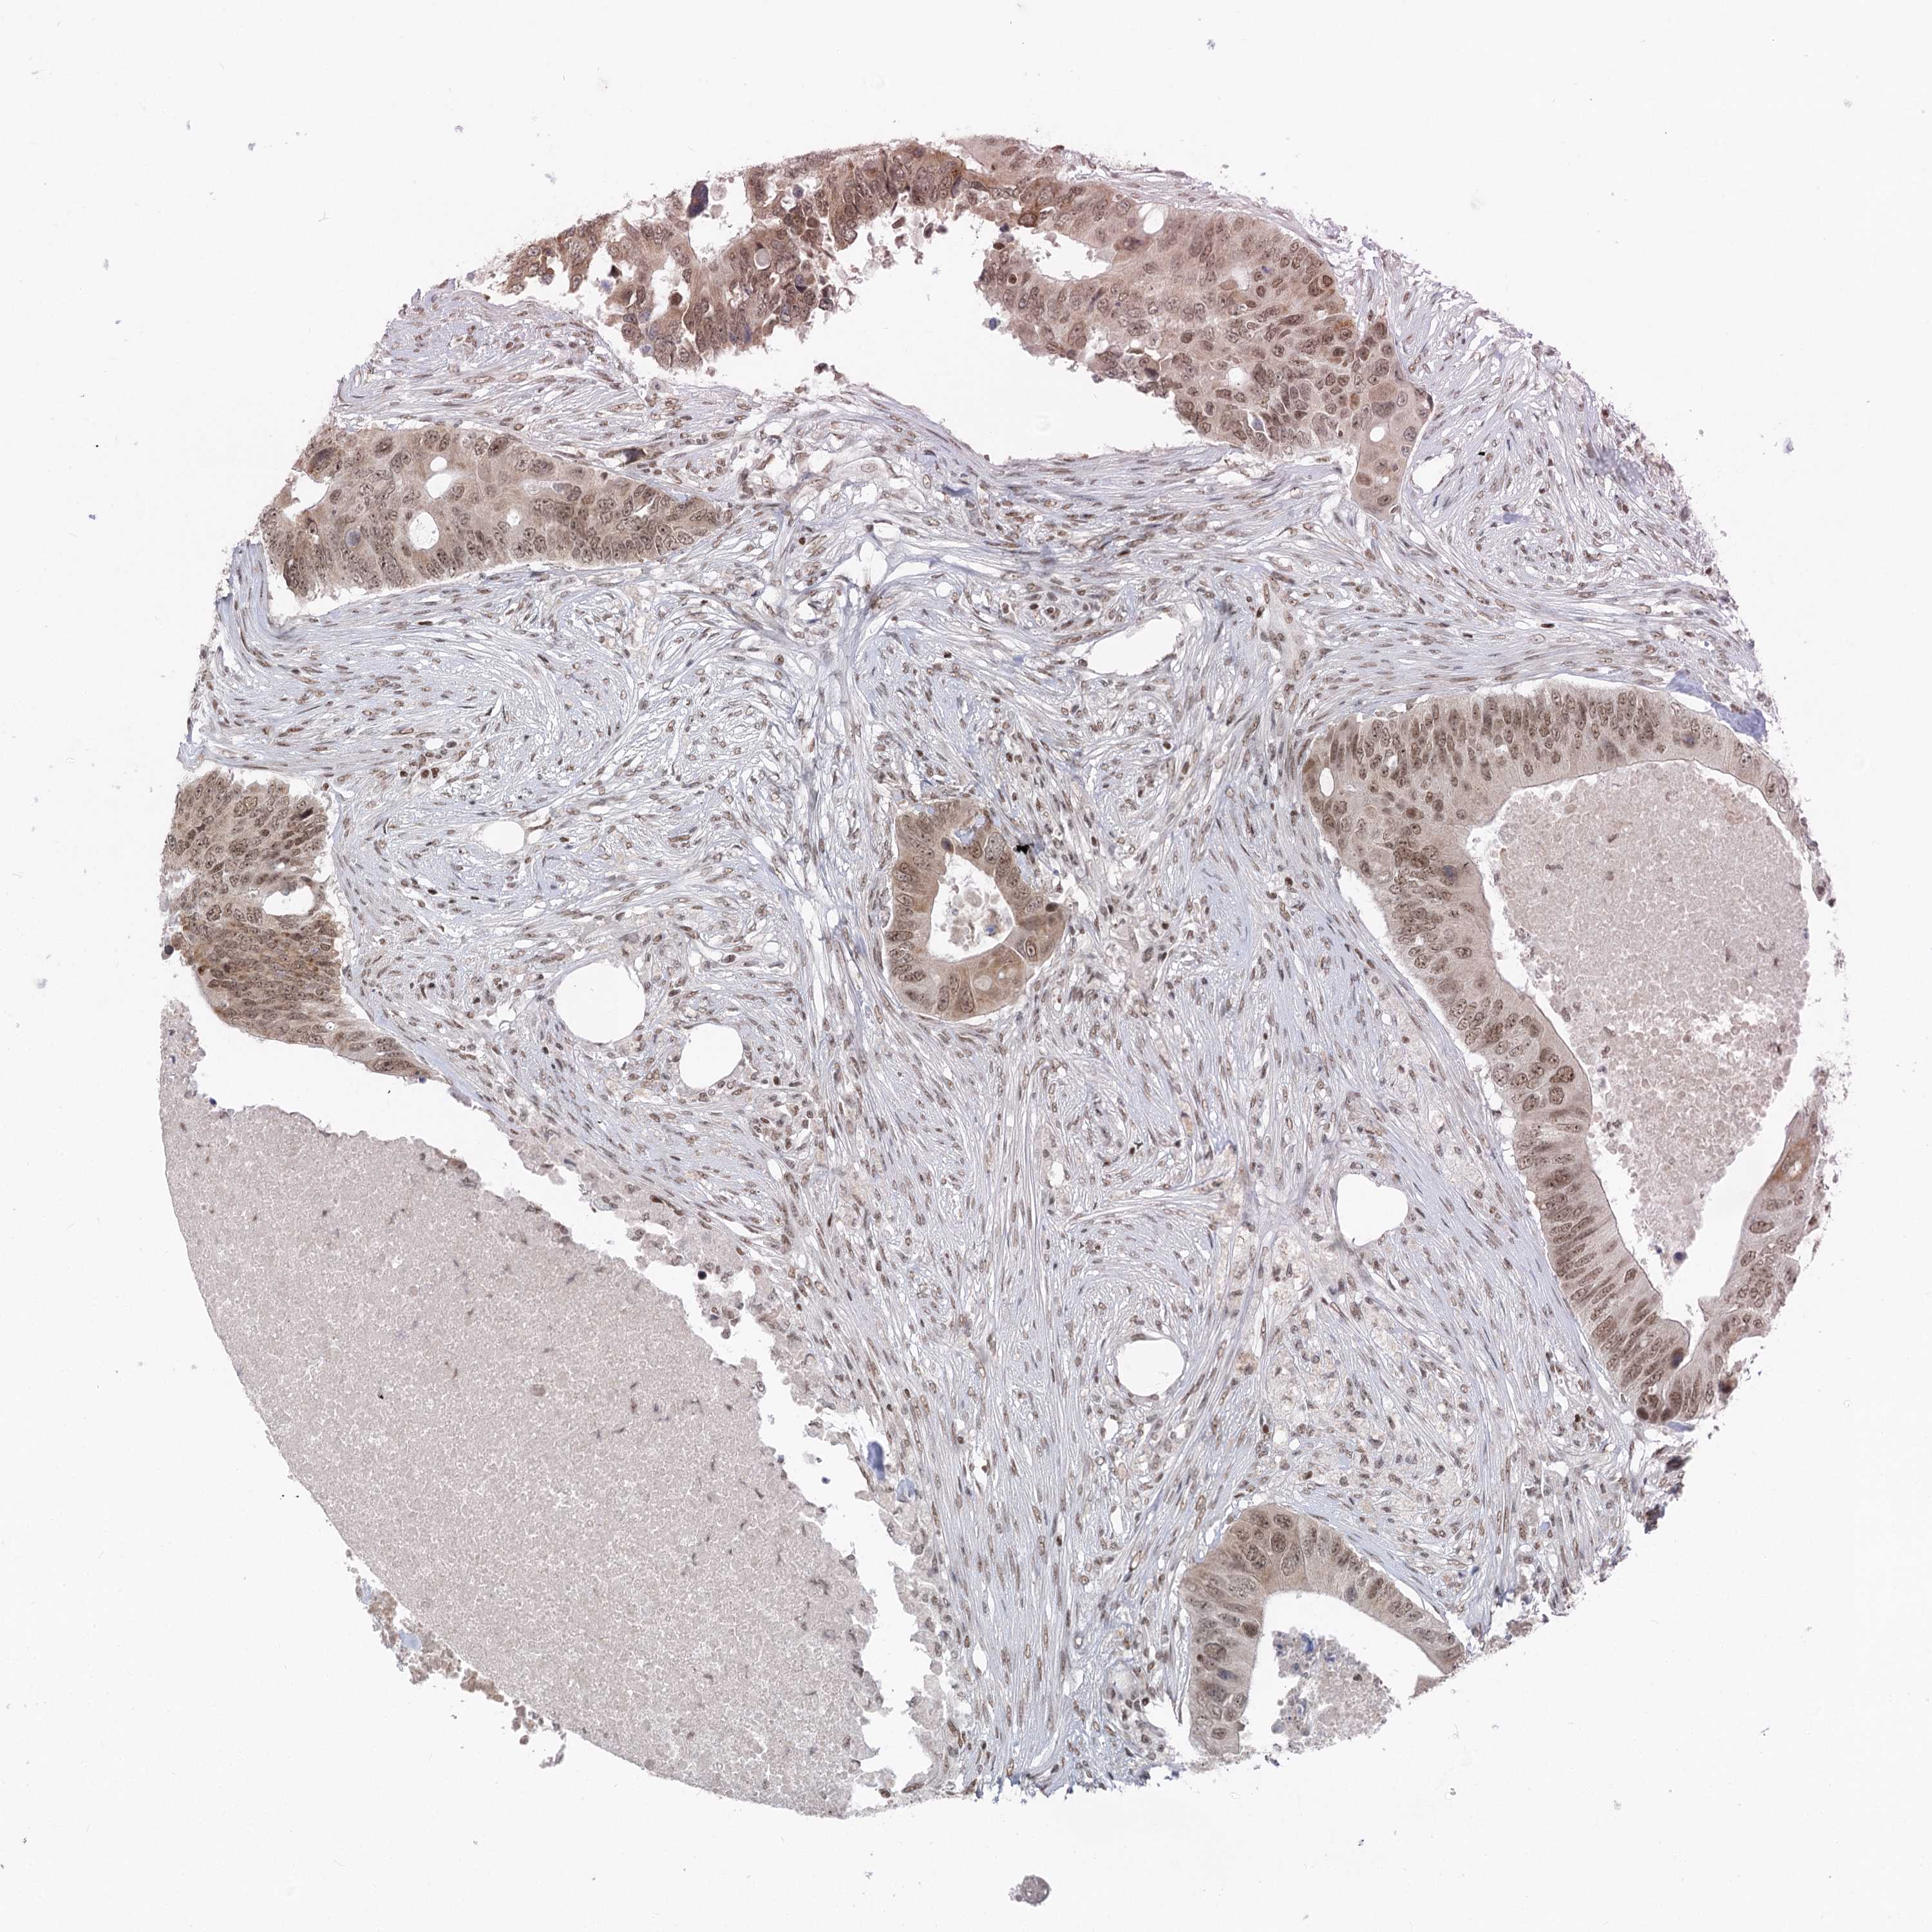

CANCER COLORECTAL CANCER Show tissue menu

Colorectal cancer

Human cancer

Colon adenocarcinoma